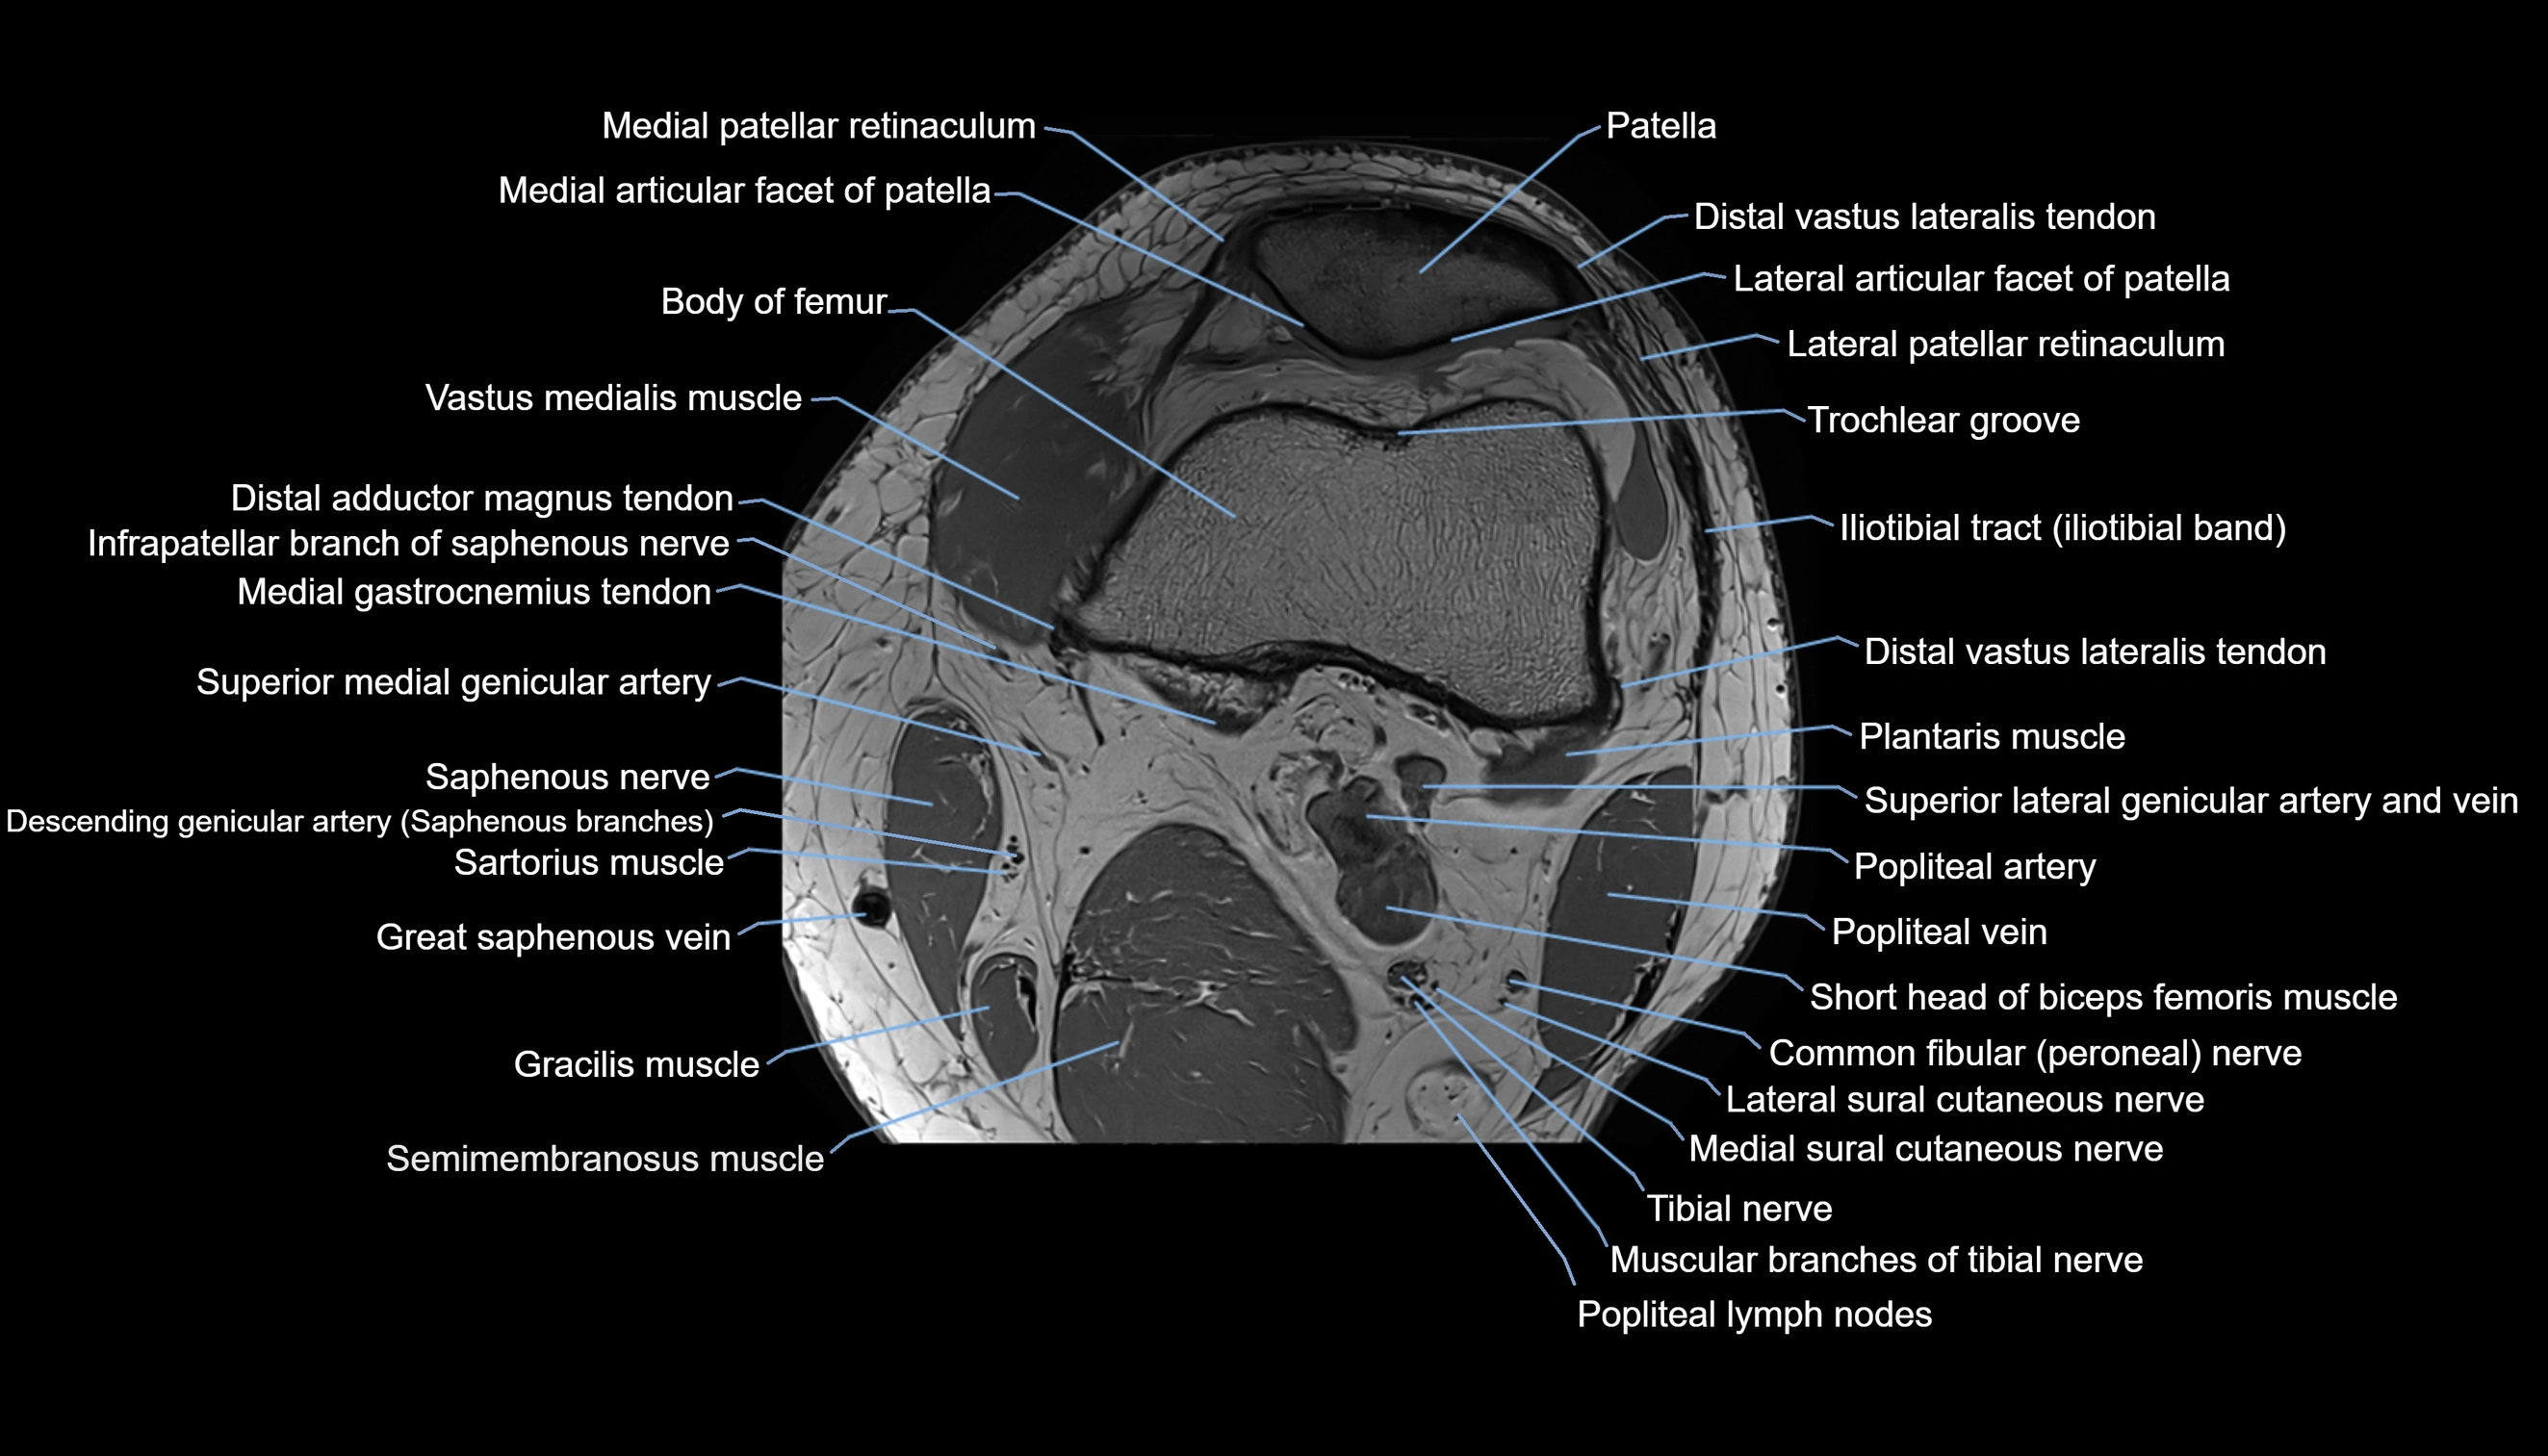

- Body of femur

- Distal adductor magnus tendon

- Distal vastus lateralis tendon

- Distal vastus medialis tendon

- Fibularis longus muscle (peroneus longus muscle)

- Infrapatellar branch of saphenous nerve

- Lateral condyle of femur

- Lateral gastrocnemius tendon

- Lateral patellar retinaculum

- Lateral sural cutaneous nerve

- Medial articular facet of patella

- Medial gastrocnemius tendon

- Medial patellar retinaculum

- Medial sural cutaneous nerve

- Muscular branches of tibial nerve

- Patella

- Popliteal artery

- Popliteal lymph nodes

- Popliteal vein

- Saphenous nerve

- Sartorius muscle

- Semimembranosus muscle

- Superior lateral genicular artery

- Superior lateral genicular vein

- Tibial nerve

- Trochlear groove

- Vastus Lateralis Obliquus Muscle

- Vastus lateralis muscle

- Vastus medialis muscle

- great saphenous vein